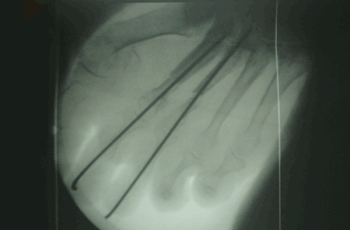

RESULTADOS

Caso 1: Hallux Valgus del Adulto